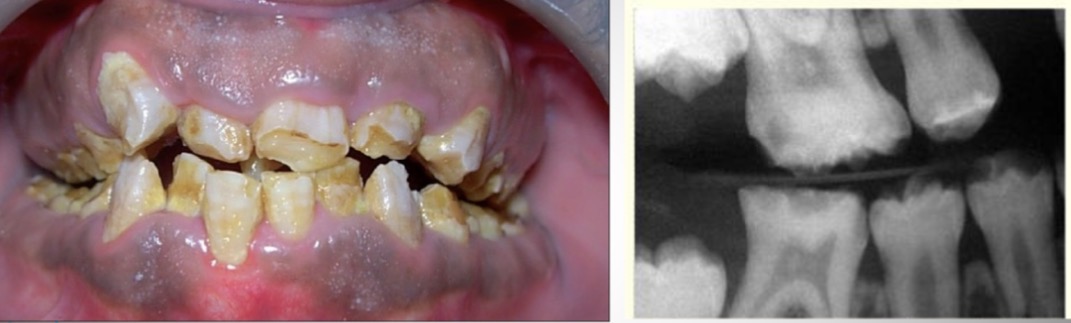

What is this condition?

Supernumerary teeth